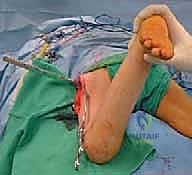

5. التدوير (Derotation)

هنا تكمن مهارة الجراح؛ يتم تدوير الجزء السفلي من عظم الفخذ (الساق بأكملها) إلى الخارج بالدرجة المطلوبة تماماً (عادة بين 20 إلى 30 درجة) لتصحيح الانحراف الأمامي المفرط وإعادة القدم إلى وضعية الاستقامة الطبيعية.

7. الإغلاق والتعافي

يتم التأكد من الاستقامة النهائية ومجال الحركة الميكانيكي للمفصل، ثم تُغلق الأنسجة والجلد بخياطة تجميلية دقيقة لتقليل الندبات.